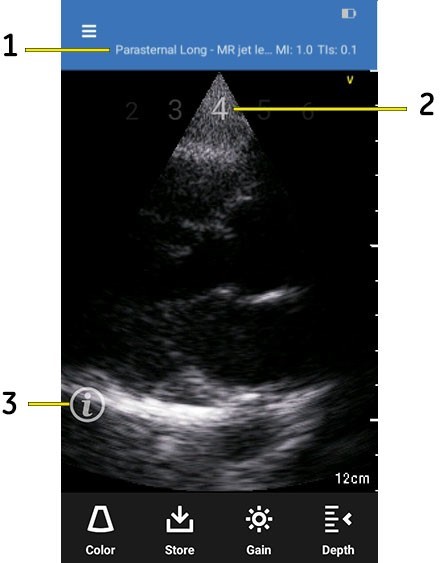

The live scan screen displays the following interface elements for the current protocol:

Interface elements

- Current step name - displays the step text. For example, Parasternal Long Axis

- Step number - displays previous (for example 3), current (4) and next step numbers (5)

- Info icon - invokes Scan Coach help windows for current step

4. Press the Info (i’) icon to access Scan Coach reference help for the current step.